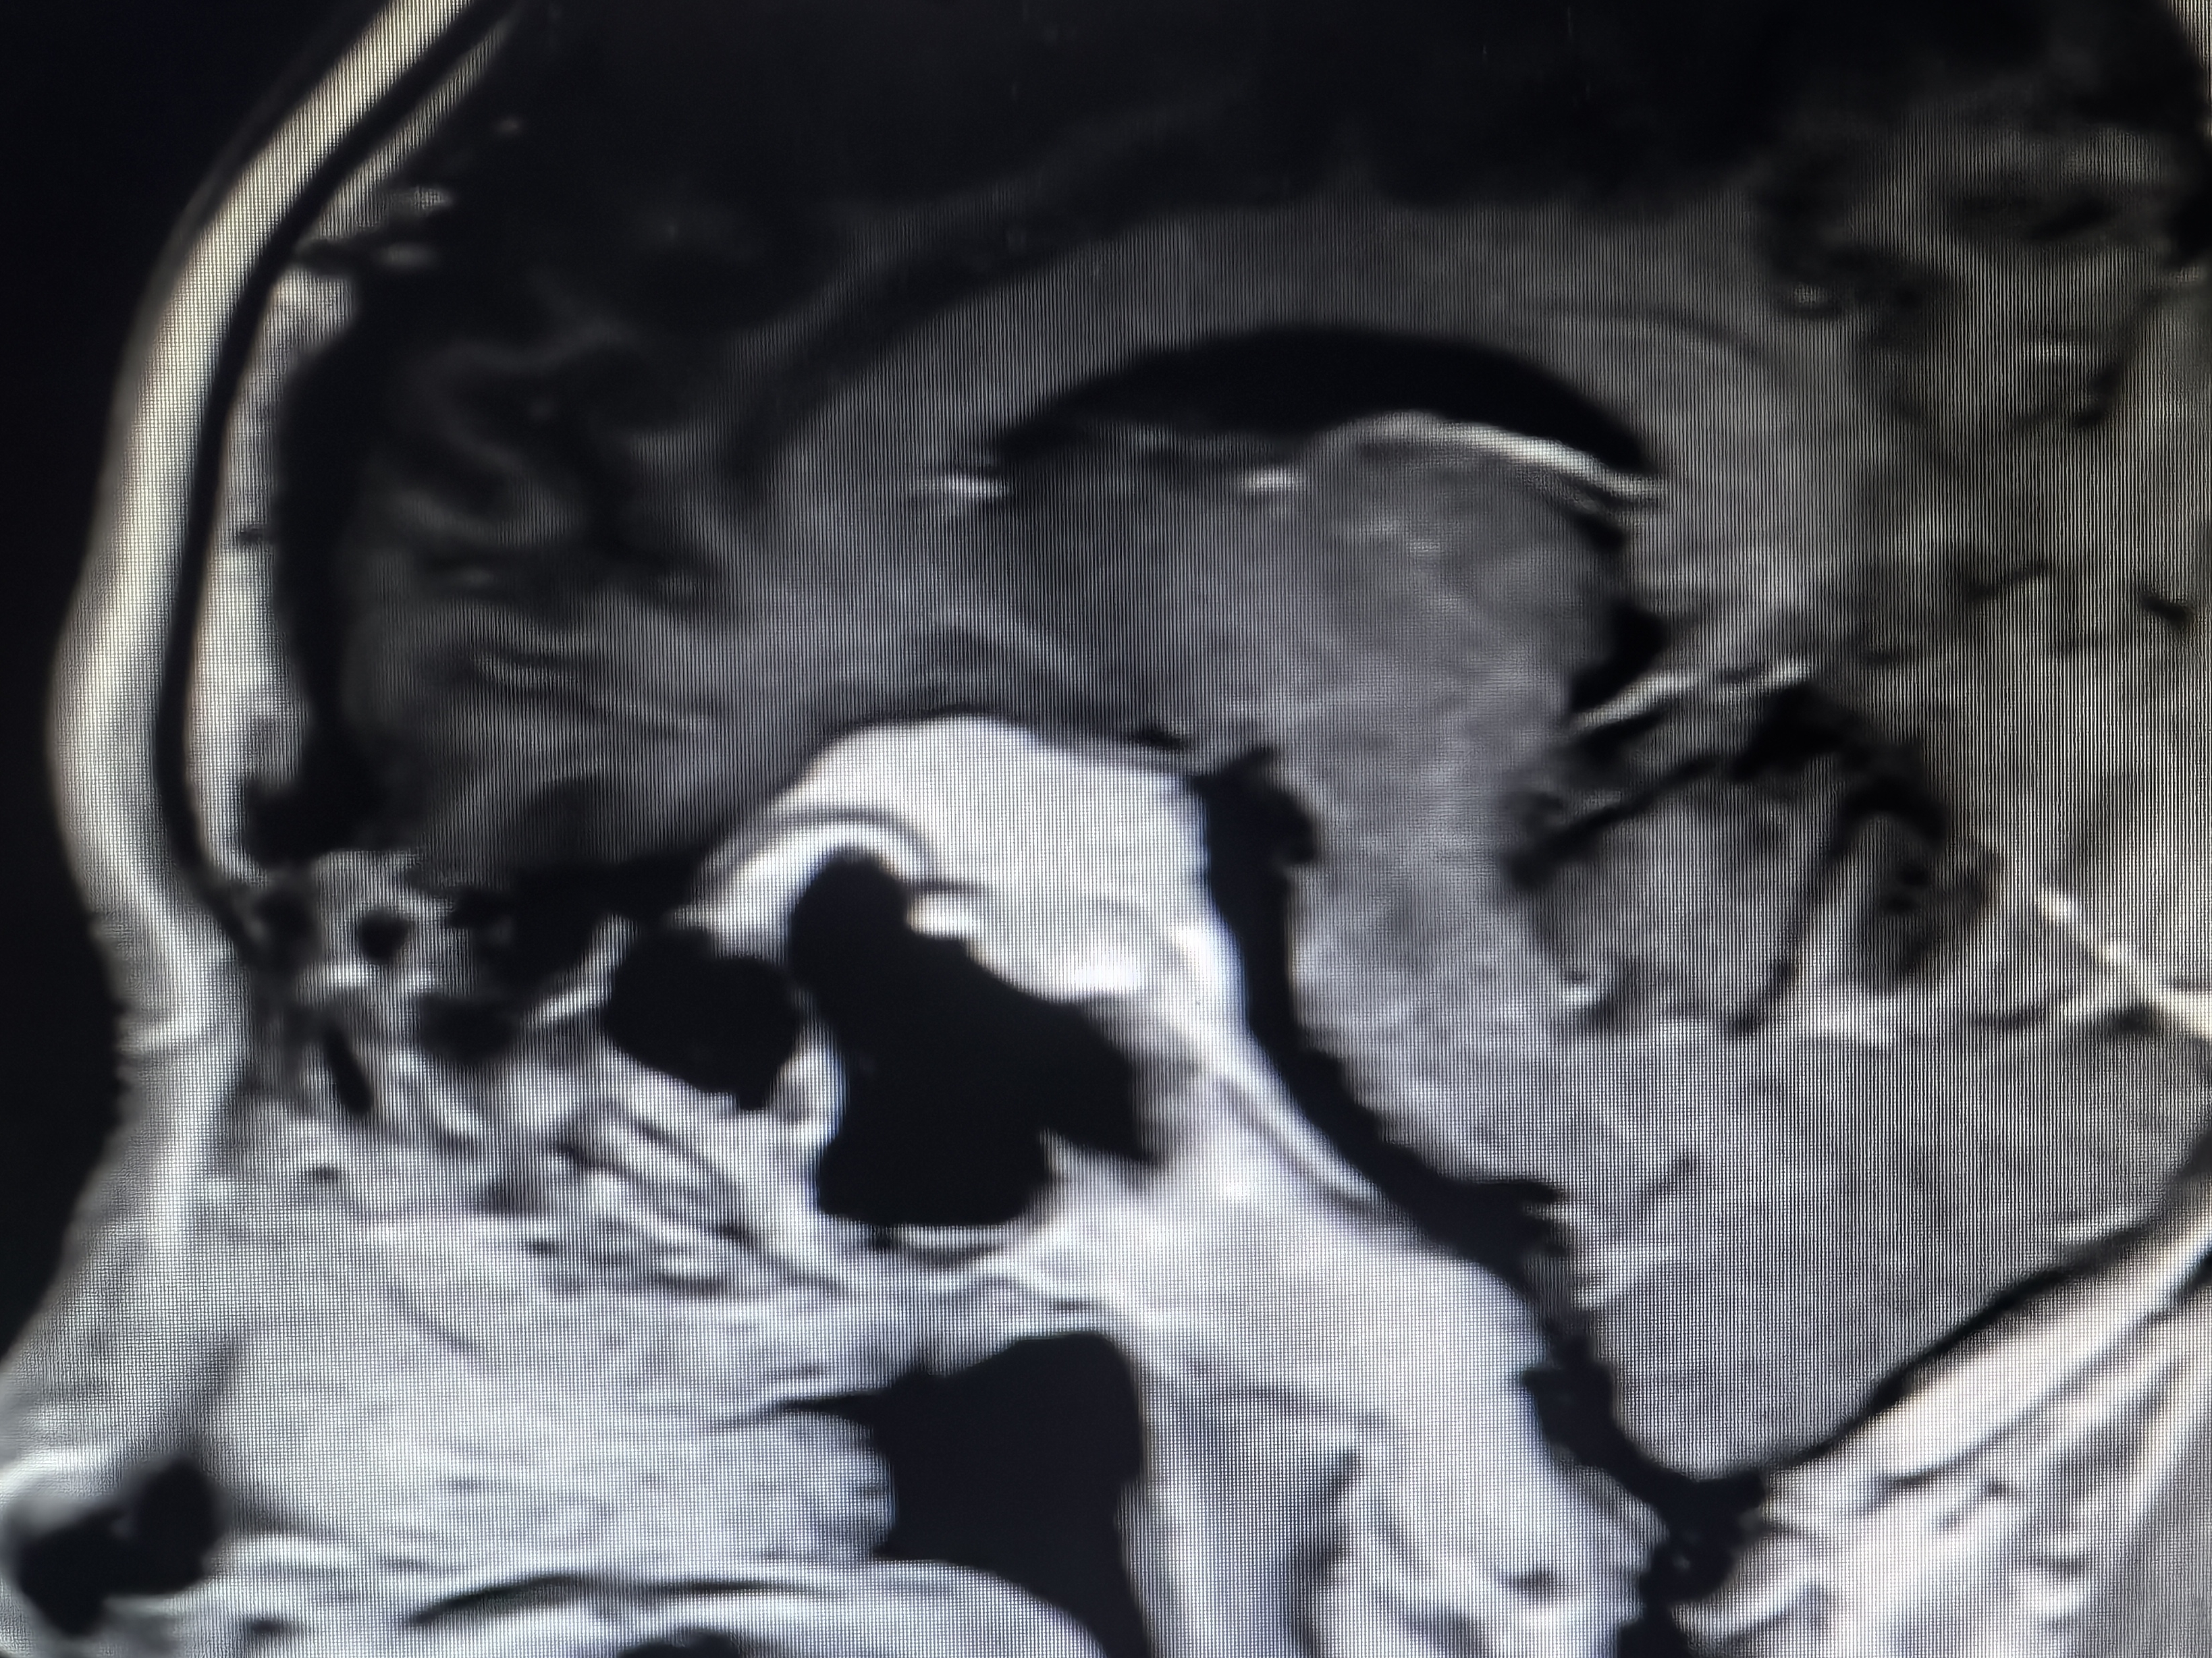

下面展示本病房几例病例:

病例一